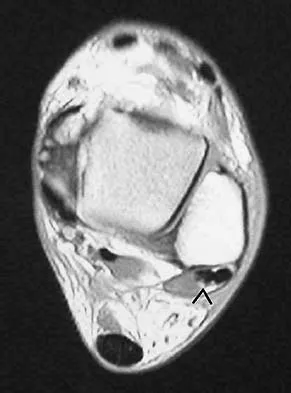

Question 59 High Yield

What structure (arrow) is shown in Figure 24?

Detailed Explanation